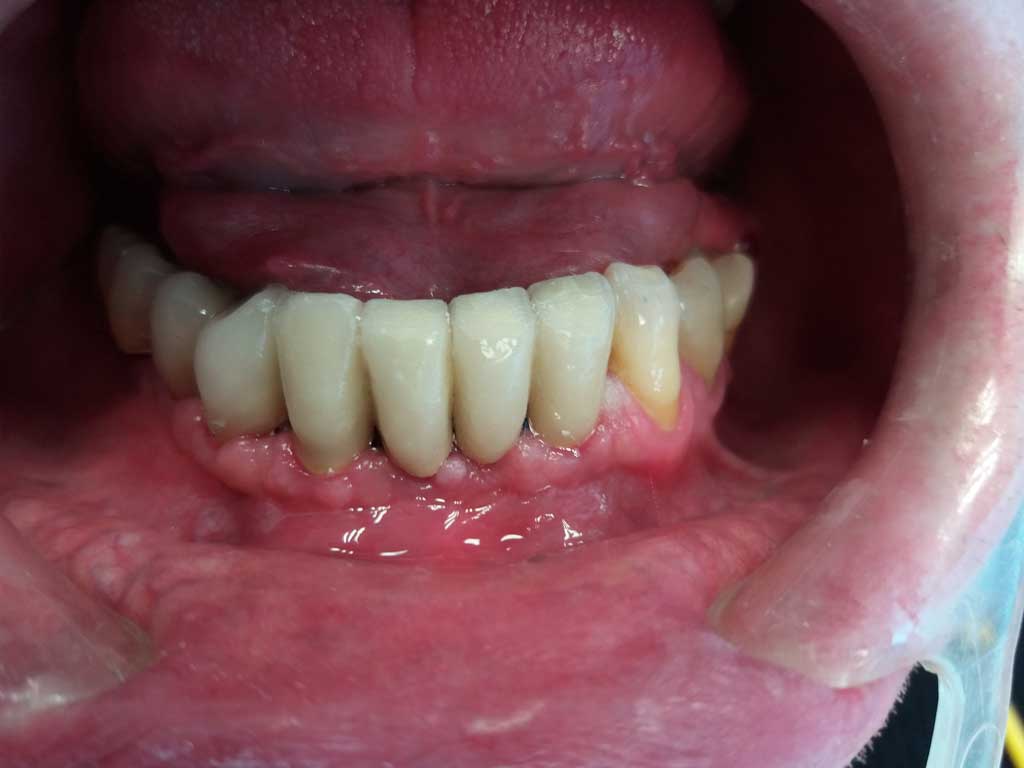

A gengiva completamente guarita , dopo 3 mesi circa dall'inserimento degli impianti, è stato consegnato il lavoro definitivo.

Il paziente è rimasto molto soddisfatto e per noi questa è la cosa più importante.

DOPO